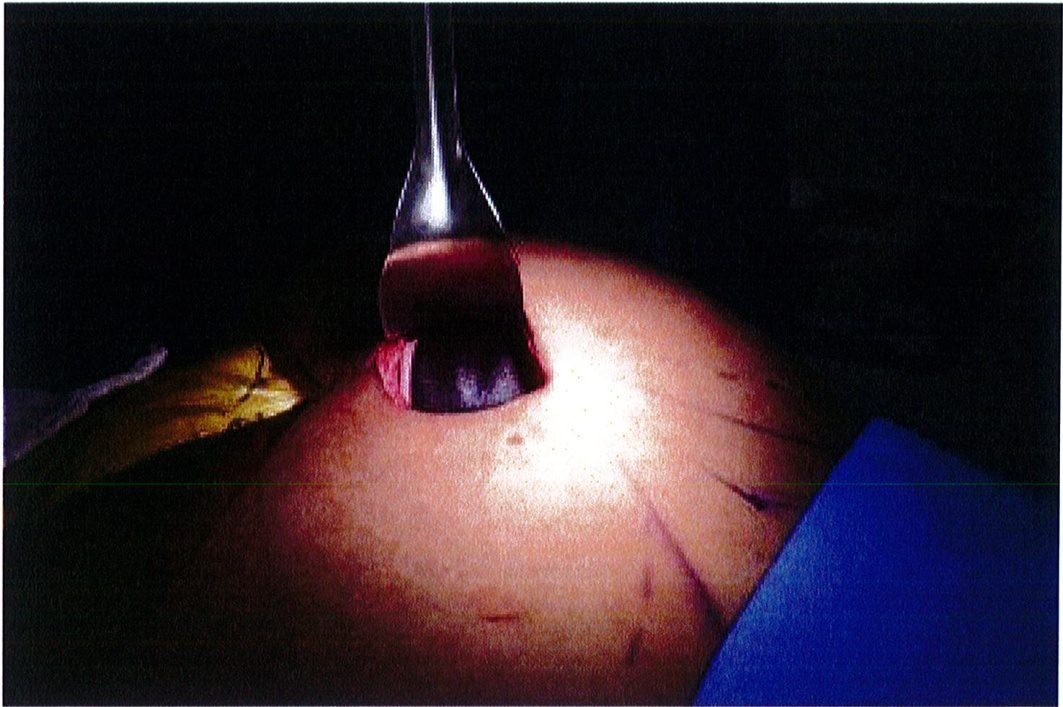

Dụng cụ bóc tách hai đầu tù, hình tròn được sử dụng để phân tách mặt phẳng vô mạch đã được bộc lộ bằng cách tiêm dung dịch trước đó, nhằm bảo tồn tối đa vách và lớp cân mạc. Nên thực hiện bóc tách từ trong ra ngoài, từ trên xuống dưới với một dụng cụ banh có đèn sợi quang (Hình 10). Để tách các vách ngăn, sử dụng một cây bóc tách dài có một đầu nhọn hoặc kéo dài (Hình 11). Các nhánh động mạch mông trên, mông dưới và một số mạch nuôi cho vùng cân mạc được đốt điện. Hãy chắc chắn

Hình. 9. Đánh dấu các mốc giải phẫu quan trọng. (A) Đường rạch cân cơ mông lớn bắt đầu từ bờ ngoài xương cùng (B) Bắt đầu bóc tách lớp cân từ đường rạch ban đầu (Trích từ de la Pena JA, Rubio OV, Cano JP, et al. Subfascial Gluteal aug- mentation. Clin Plast Surg 2006;33:411; đã xin phép trước khi đăng tải.)

Extent of area undermined